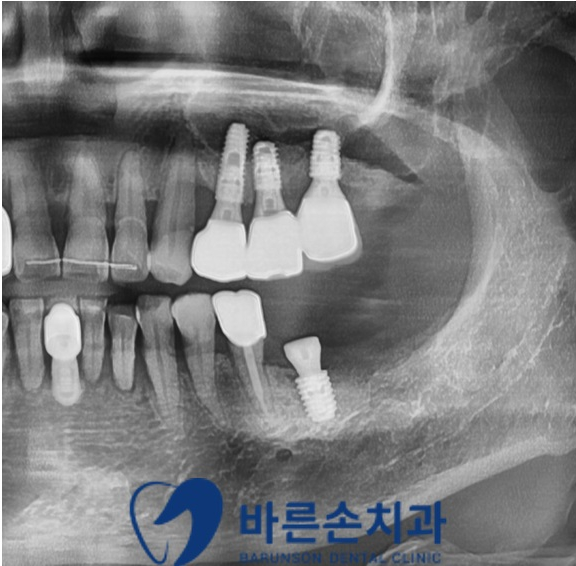

발치와 동시

뼈이식과 함께 임플란트 식립 후의 파노라마 사진입니다

치조골 손상이 심해 많은 양의 뼈이식이 필요하였지만

좋은 위치에 안정적으로 임플란트 식립이 잘 되었습니다